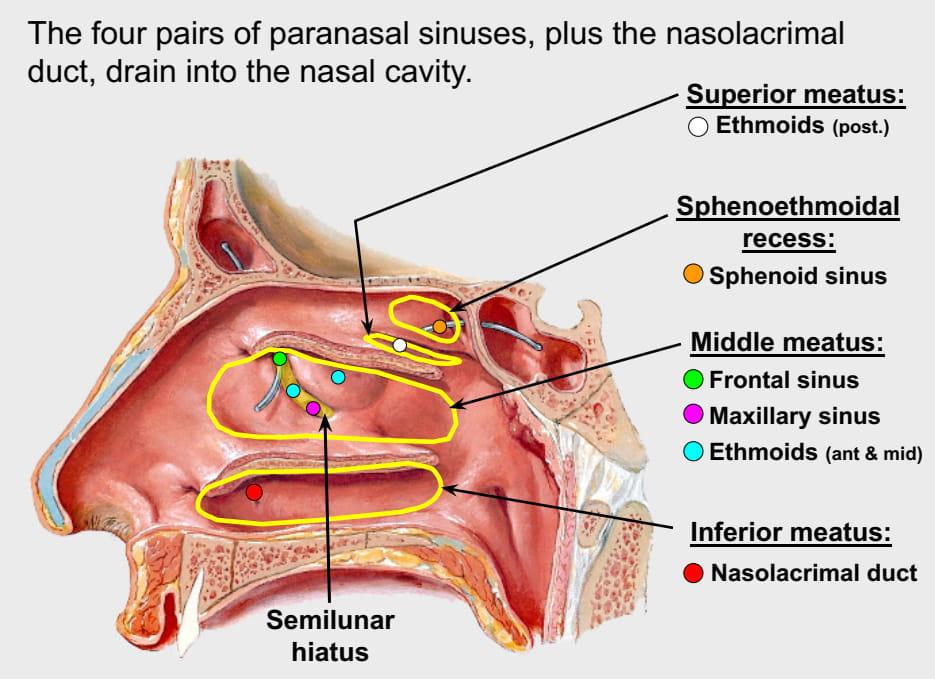

Paranasal sinuses

鼻旁竇,濕潤呼吸的空氣

Frontal sinus

神經皆CN V1

- Anterior ethmoid a.

- Supraorbital a./n.

- Supratrochlear (滑車上) a./n.

Maxillary sinus

來自Maxillary a. 3rd Part, Maxillary division

- Ant./mid. sup. alveolar a./n.

- Post. sup. alveolar a./n.

Ethmoid sinus

ethmoid bulla

Mid. ethmoid sinus 開口

Sphenoid sinus